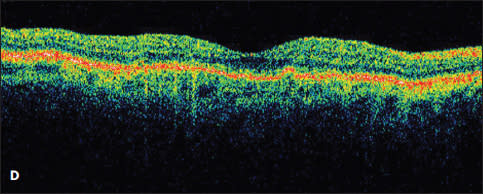

Figure 3. A patient with a new serous PED and CNV identified by ICG was treated with ranibizumab, followed by monthly aflibercept (A and B). Despite treatment, the PED worsened with increasing size and SRF (C). The patient then underwent PDT to the area of the choroidal feeder vessel without resolution (D).

Case 4. Such was the case of a 56-year-old woman who presented with a large serous PED with small amount of subretinal fluid (Figure 4A). Her vision had dropped from 20/20 to 20/400. Fluorescein angiography revealed a notch at the inferior-temporal border of the PED. ICG angiography showed a large, dilated vessel at 7 o’clock (Figure 4B).

The patient was treated with intravitreal aflibercept without improvement and then was switched to intravitreal ranibizumab. Despite treatment, the PED grew in size, and the subretinal fluid increased (Figure 4C). She was re-evaluated with ICG angiography (Figure 4D), and then was treated with PDT to the area of the choroidal vessel identified at 7 o’clock.